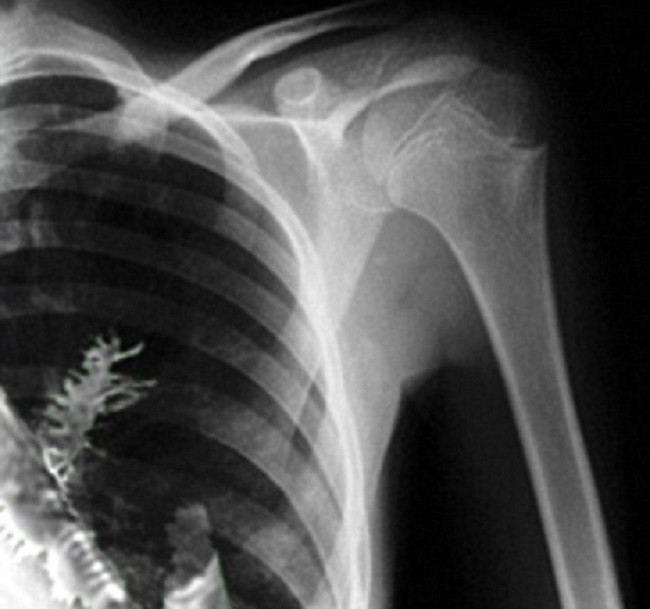

| Phim X-quang chụp cây linh sam mọc trong phổi anh Artyom Sidorkin. |